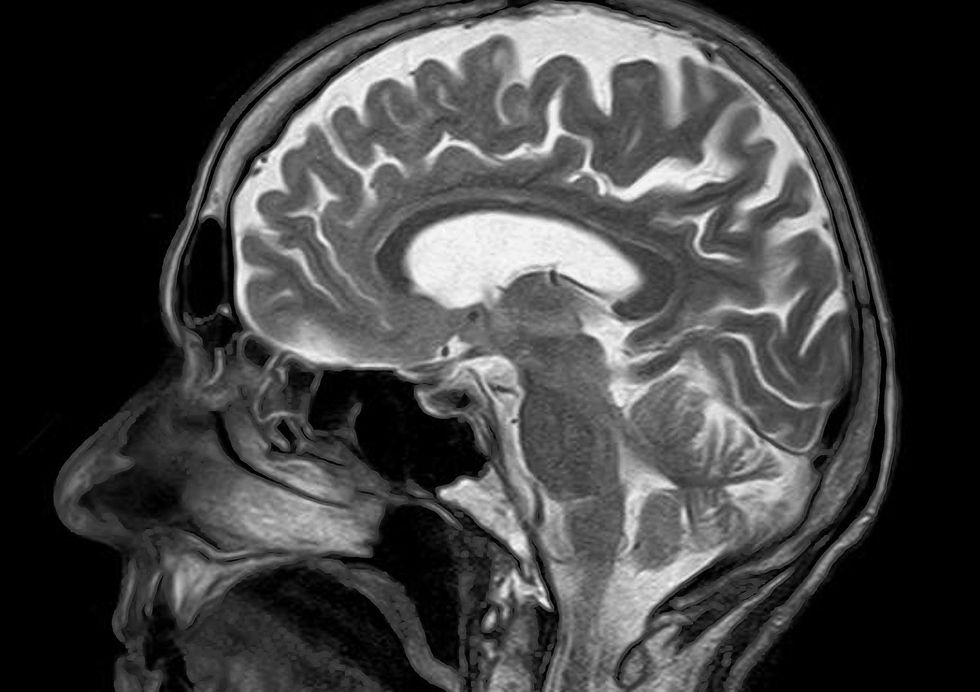

The main development from this study is that it’s non-invasive. This means that subjects do not require surgical implants. Instead, brain activity is measured using a functional magnetic resonance imaging (fMRI) scanner.

In the study, individuals listened to hours of podcasts in the scanner. Then, given the participant’s consent to have their thoughts decoded, they listened to a new story and the machine-generated corresponding texts from brain activity.